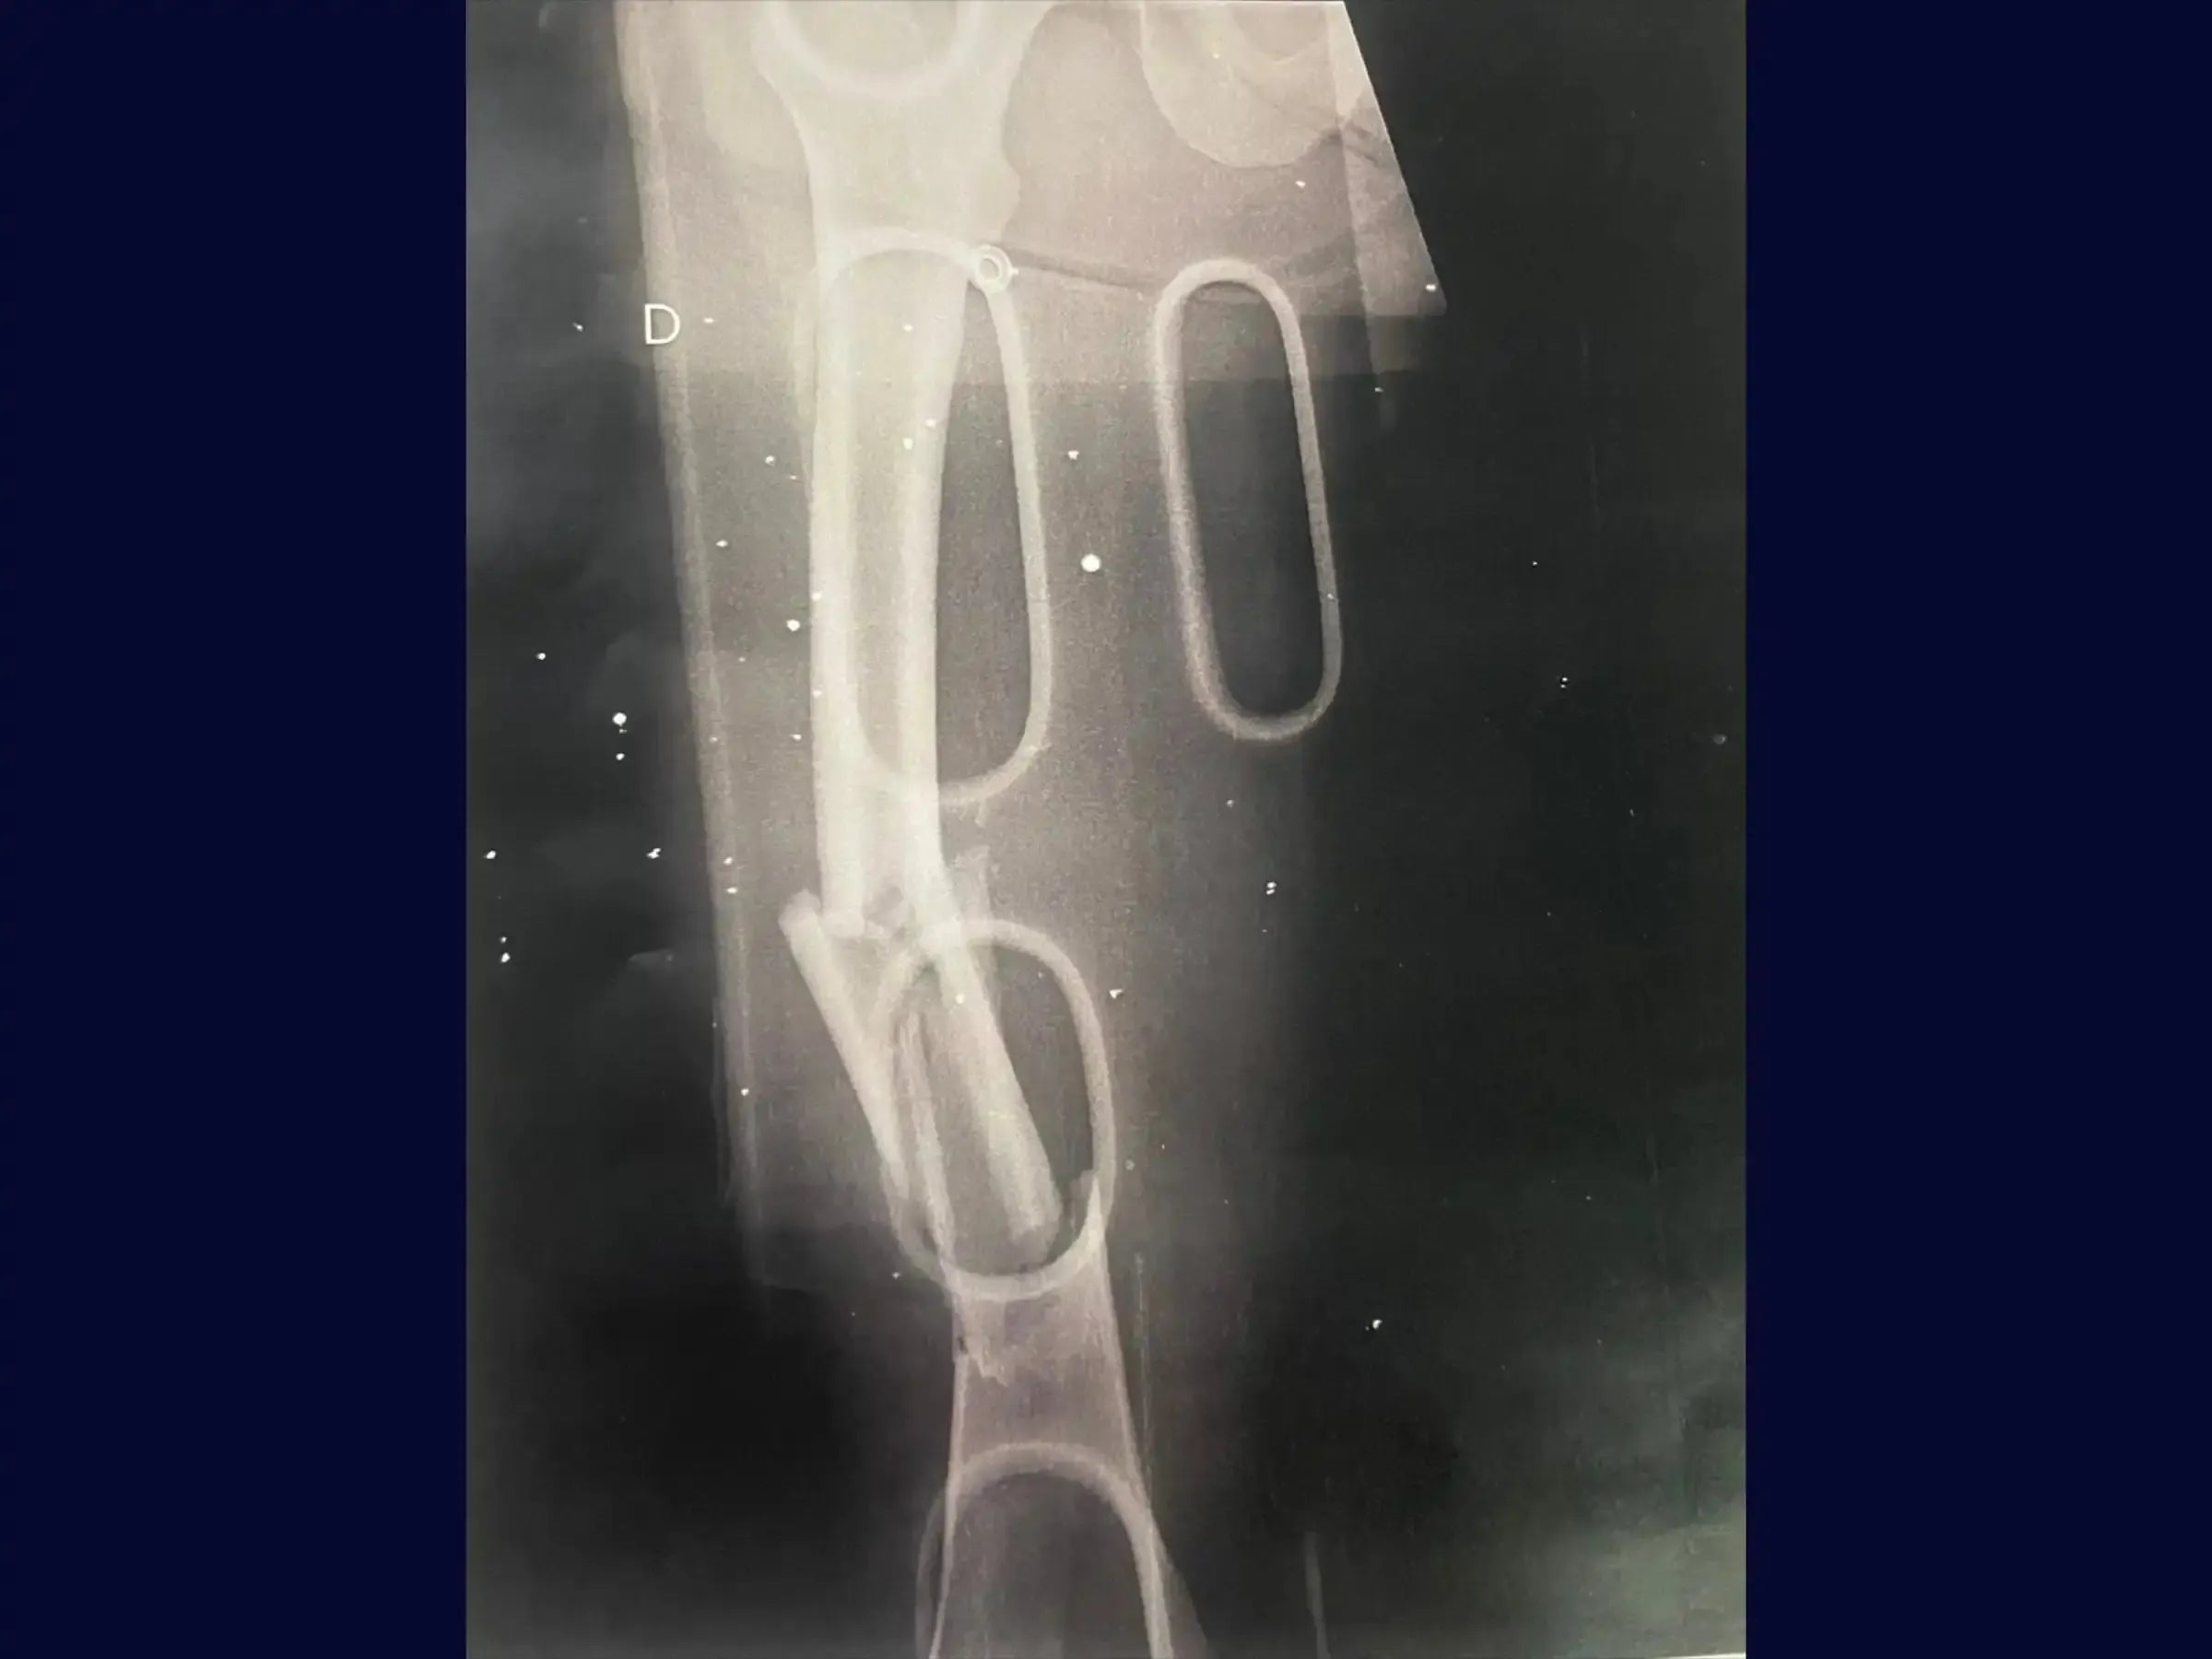

- Fresagem e Medição da Haste: Desenvolva a habilidade de fresar o canal medular para permitir a introdução de uma haste intramedular de diâmetro adequado, e realize a medição da haste utilizando o próprio fio guia com auxílio de dois fios similares.

- Introdução da Haste Intramedular Retrógrada: Aprenda a introduzir a haste de forma retrógrada com conferência constante das imagens fluoroscópicas, garantindo que a extremidade da haste direcionada ao quadril ultrapasse o pequeno trocânter para evitar estresse e risco de fratura subtrocantérica.

- Resultados Otimizados: Obtenha resultados cirúrgicos onde a haste está posicionada acima do pequeno trocânter e seguindo a linha de Blumensatt, sem proeminências no joelho, permitindo certa mobilidade no pós-operatório.